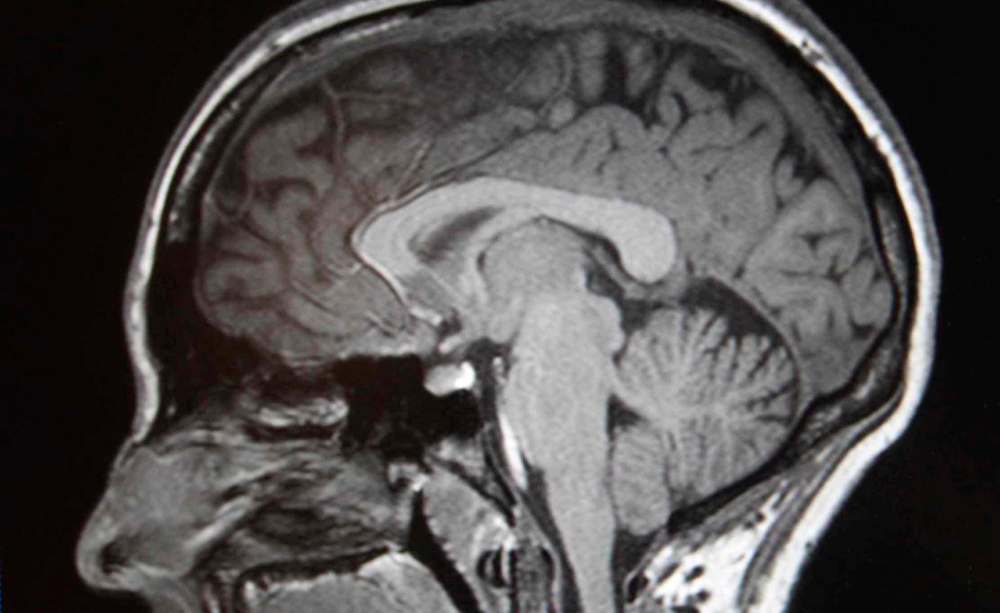

A Winnipeg brain surgeon, who was hired five years ago to establish a groundbreaking epilepsy program, has decided to leave Manitoba because he says the province has failed to fulfil its promise to fund it.

“It’s an important cause close to my heart,” said Serletis, who specializes in neuroengineering. He led the formation of a multidisciplinary team that developed a proposal for comprehensive pediatric and adult epilepsy services. He was honoured by Doctors Manitoba this year for his work, which has helped to recruit other specialists to Manitoba.

By starting with a surgeon, “it gives some reassurance to neurologists that there might be a commitment towards actually developing a program like this,” said Serletis. Epilepsy is a unique specialty that’s like a “team sport” that requires a neurosurgeon, neurologists, radiologists, electroencephalogram (EEG) technicians and dedicated nurses, he said. When he arrived, the adult epilepsy unit was located on an orthopedic ward where nurses weren’t trained in seizure management. On the pediatric side, the last neurologists who specialized in epilepsy had left the province, he said.